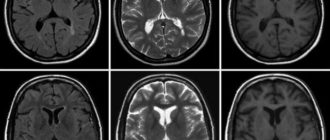

Самостоятельная расшифровка МРТ головного мозга: результаты, заключение по снимкам МРТ — один из самых